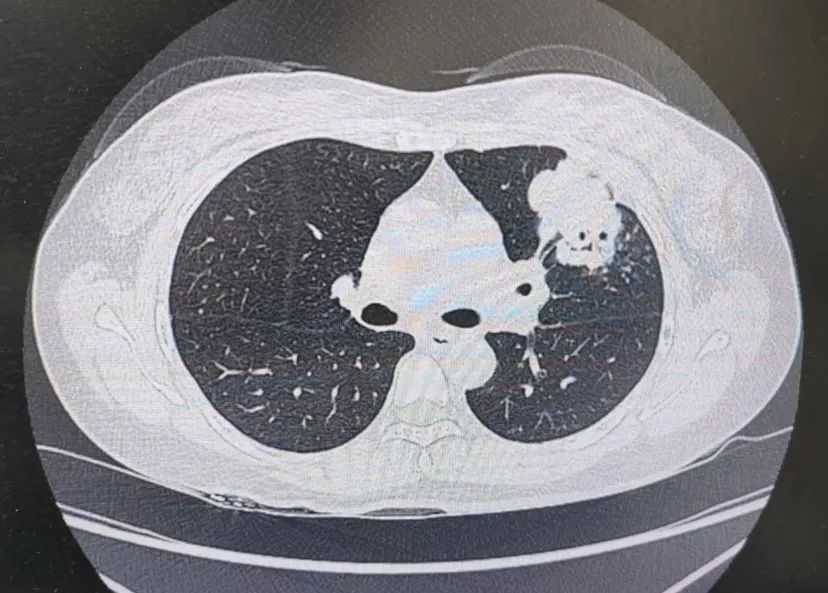

患者肺部CT影像

“一般来说,肺炎经过一周的抗感染治疗,病灶会有所吸收。但陈女士的肺部阴影纹丝不动,这种情况必须提高警惕。”宋刚主任团队立即启动了更深入的“三部精准诊断”程序:

1、支气管镜探查:快速排除气道新生物;

2、肿瘤标志物追踪:多项血清指标显著升高,直指肿瘤可能;

3、CT引导下穿刺活检:病理诊断为左肺上叶腺癌。

肺炎型肺癌,因其影像学表现与普通肺炎极为相似,临床上误诊率极高。然而确诊仅是第一步。宋刚主任当天即召集肿瘤科、病理科、影像科等多学科专家会诊,为陈女士制定个体化治疗方案。